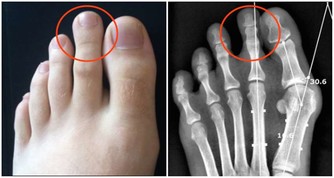

1、口腔疾病

當口腔內出現疾病時,也可能會導致人出現口乾、口苦的問題,比如說其實口腔潰瘍,牙齦炎,牙周炎等,這些疾病都可能會導致人出現口苦口乾的症狀。尤其是晚上不刷牙時,第二天這種症狀會更加明顯。